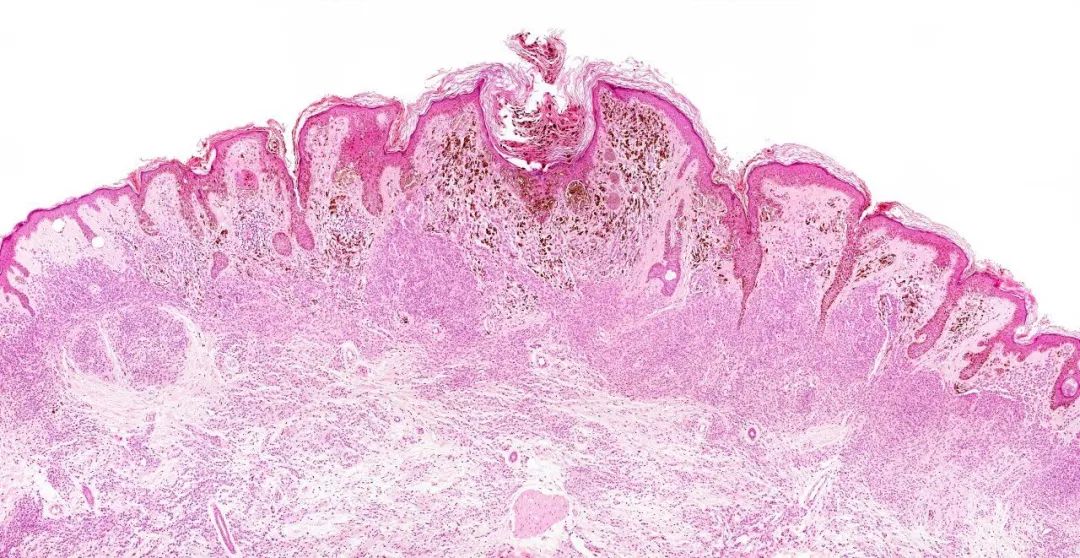

这项研究结果被发表在顶级医学期刊《自然》(Nature)杂志上。研究人员发现,黑色素瘤细胞穿过淋巴结并吸收了一层保护性涂层,使它们能够在高水平的氧化应激中存活并继续形成远处的肿瘤(图1)

图1:上方为黑色素瘤细胞(图片来源:UT Southwestern Medical Center)